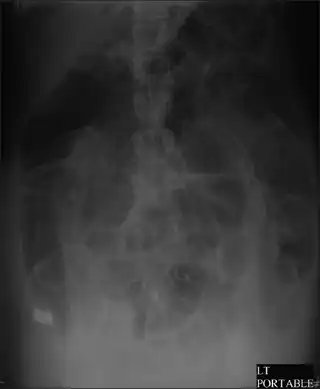

Diagnosis starts with physical exam, observation, and interview of the patient. Imaging to diagnose dilation of the colon involves one view abdominal xray or obstruction series (PA chest, erect abdomen, and supine abdomen images). If further imaging is needed CT may be ordered.[13]